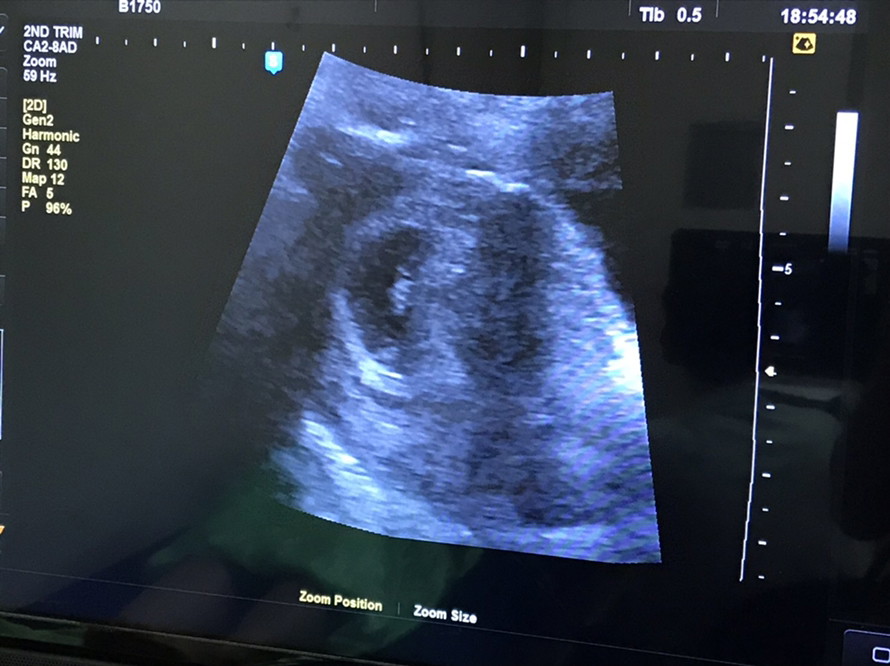

ซาวด์เจอน้องกี่วีคค่ะะ

ตอนนี้ท้องได้ประมาน 6วีคแล้วค่ะ ไปซาวด์หมอเจอแต่ถุงตั้งครรภ์ยังไม่เจอตัวอ่อน ปกติกี่วีคถึงจะเจอตัวอ่อนค่ะ

วันนี้ไปซาวด์มาค่ะ 6w6d เจอแต่ถุงค่ะ คุณหมอนัดอีกครั้ง 3สัปดาห์ค่ะ ตื่นเต้นมากๆค่ะลูกคนแรก

6W เจอแต่ถุงเล็กๆ เช่นกันค่ะ หมอนัดอีก2W ไปซาวด์ใหม่ คิดว่าน่าจะเห็นน้องตัวเล็กมากๆค่ะ